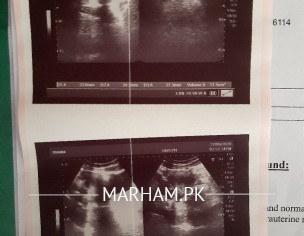

i usually ovulate on 11th or 12th day of my cycle and have EWCM. but this time i had watery Cervical mucus with clouds which were strechy but it wasn't like EWCM and slippery. my right ovary is enlarged and multiple follicles are seen on ultrasound. my cycles are regular but last month i only bleeded for 2 days . i never had heavy bleeding but this time it was less. my weight is 71 and height is 5.8. visited gynecologist she told the problem is yet not too severe for harmonal medication. suggested folic acid . my lh , fsh , prolactin, tsh and insulin are normal. please tell me is it getting worse? can i conceive naturally? really worried.

Please reduce your weight. It should be around 60-62 kg for your height. Thus will increase your chances of conception. There is no dominant follicle in your scan. So reducing weight is necessary. If after weight ready reduction pregnancy doesn’t occur then ovulation drugs are indicated.

mam i am working on my weight it was 75 now its 71 ... in sha ALLAH i will cut it down more as well ... plus mam this ultrasound was done on the 6th day of my cycle. 6th day of my follicular phase